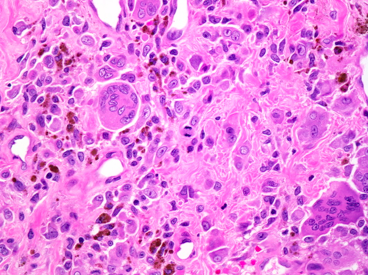

Pathological findings crystal arthropathy?

* Cytology – joint fluid shows needle-shaped crystals

* Histology – amorphous eosinophilic debris (giant cells), will not see crystals, another form of crystal arthropathy that can look similar = pyrophosphate arthropathy